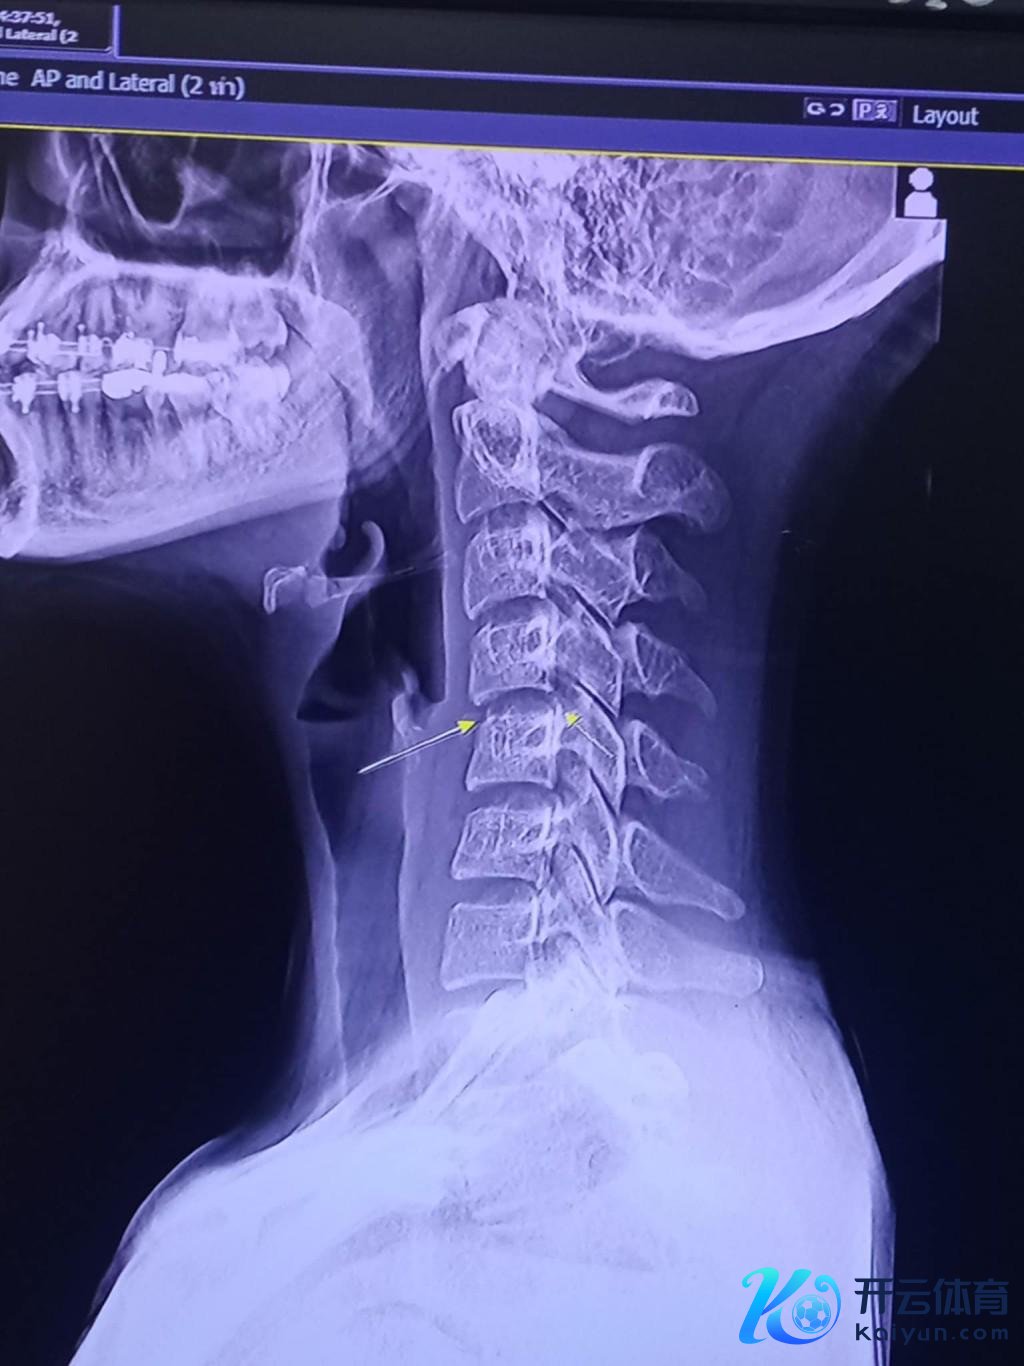

但事实其实是第一次推拿的时候就还是导致了她的颈部第三要害错位,难受是因为颈部的错位挤压到了颈椎里面的神经元。

但她将雅达送到病院查抄发现还是来不足了,她的颈椎还是严重错位况兼无法归附,颈椎里面的神经元还是接近断裂。

而神经元的断裂代表着她的全身肌肉与大脑开辟不起谋划,雅达最终因为血管感染再加上脑部与颈椎肿胀充血激发并发症,直到她的全身器官弃世。